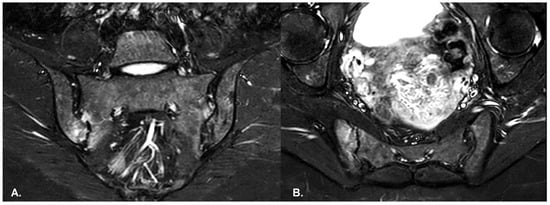

- BME is evident in low signal T1w, hyper signal T2w, STIR images and +C T1w Fat-Sat, similar to blood vessels and spinal fluid; the signal intensity is directly proportional to the inflammation activity. It is usually located periarticular to or on the subchondral bone surfaces and it is an indicator of disease activity (Figure 4) [65].